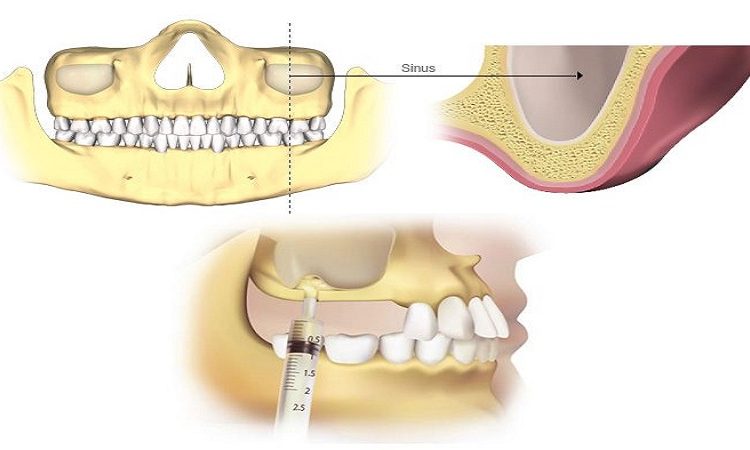

جراحی سینوس برای کاشت ایمپلنت به دو روش لیفت باز و لیفت بسته انجام می گیرد. که به طور کلی در زیر توضیح خواهیم داد که چگونه سینوس لیفت باز و بسته انجام می گیرد. سینوس لیفت باز سینوس در فک بالای افراد قرار دارد و حفرهی خالی در فک بالا و در نوک ریشهی

لیفت سینوس چیست؟ جراحی سینوس لیفت عمل لیفت سینوس جراحی است که در آن با افزودن مواد پیوندی استخوان، قاعده استخوانی محکم و کافی برای پشتیبانی ایمپلنت دندان فراهم می شود. برخی از کسانی که میخواهند ایمپلنت بگذارند، استخوان کافی ندارند و درمان ایمپلنت در آنها بدون پیوند استخوان موفق نخواهد شد. یکی از مواردی